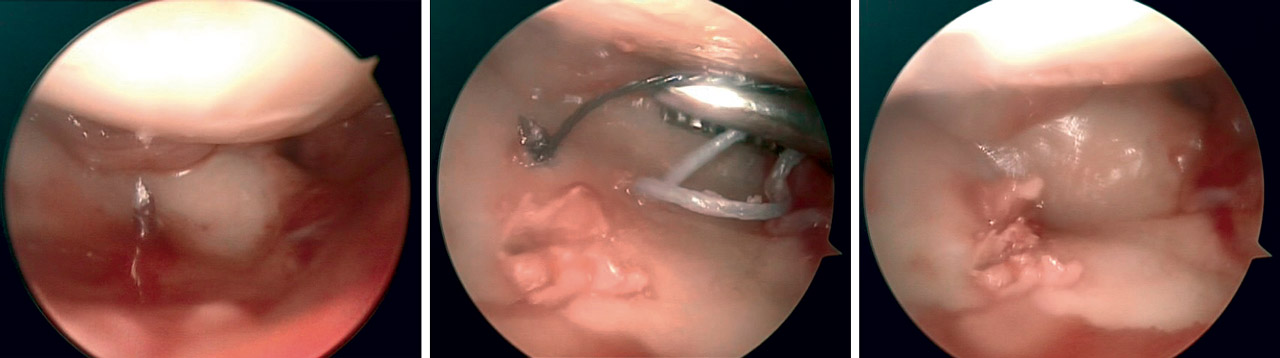

• Grado II: retensado y fijación con tornillo a compresión escafosemilunar.

• Grado III: RAFI con anclaje-reparación ligamentosa y fijación con tornillo a compresión escafosemilunar (Figura 7).

• Grado IV: en los casos en los que encontramos ligamento con suficiente entidad, se realizó una reparación directa al igual que en el grado III. En caso contrario, se realizó una plastia mediante abordaje dorsal mínimamente invasivo con tendón palmar menor.

Los tornillos escafosemilunares se retiraron a los 4 meses de la cirugía.

En roturas periféricas se realizaron suturas directas anclando el fibrocartílago a la cápsula articular. En las roturas foveales se procedió a la reinserción foveal con anclaje óseo mediante dispositivo PushLock® (Arthrex) (Figura 8). Ambas técnicas se realizaron de forma artroscópica.

En casos de lesión completa de grado III y IV realizamos desbridamiento artroscópico y fijación interna mediante tornillo percutáneo semilunopiramidal (Figura 9).

La extracción del tornillo semilunopiramidal se realizó a los 4 meses de la cirugía.